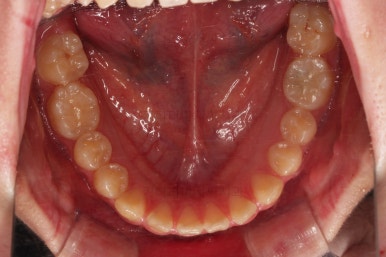

동래교정치과 초진 시 입안의 모습입니다.

치아가 벌어진 것도 벌어진 것이지만 교합이 전혀 안되고 있었어요.

틈새도 아랫니에 훨씬 많았고요.

윗니가 있는 위턱뼈가 전반적으로 아래턱에 비해 3차원으로 작은 양상이었습니다.

이번 환자분은 아랫니가 전반적으로 앞이든, 뒤든, 양옆으로든 넓어져 있는 양상이었고 그래서 아랫니에 틈도 많고 아래 앞니도 밀려나와 있는 양상인거죠.